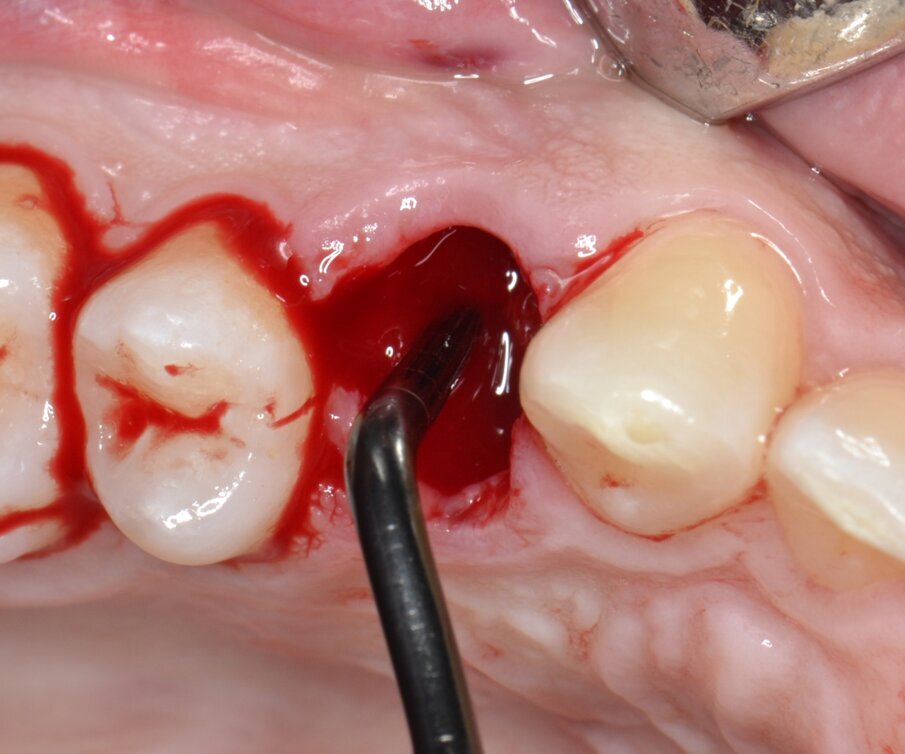

Successivamente, le due parti dell’elemento dentario vengono estratte separatamente avendo l’accortezza di usare estrema cautela nei movimenti di lussazione (Figg. 5, 6). Dopo aver completato la fase estrattiva (Fig. 7) ed aver controllato l’integrità delle pareti alveolari, il tunnel implantare viene preparato mediante l’utilizzo di inserti piezoelettrici dedicati (SUS – Surgery Ultrasonic Site, Esacrom Srl, Imola, Italia) (Fig. 8) con il duplice obiettivo di sfruttare il setto inter-radicolare per garantire una soddisfacente stabilità primaria e inserire l’impianto in posizione protesicamente guidata: una preparazione di tipo tradizionale con frese rotanti esporrebbe infatti al rischio di distruggere completamente il setto osseo che separa la radice buccale da quella palatale, costringendo l’operatore ad abortire la procedura o, in alternativa, a posizionare l’impianto in una delle due radici (Fig. 9).

Fig. 7 - Alveolo postestrattivo integro.